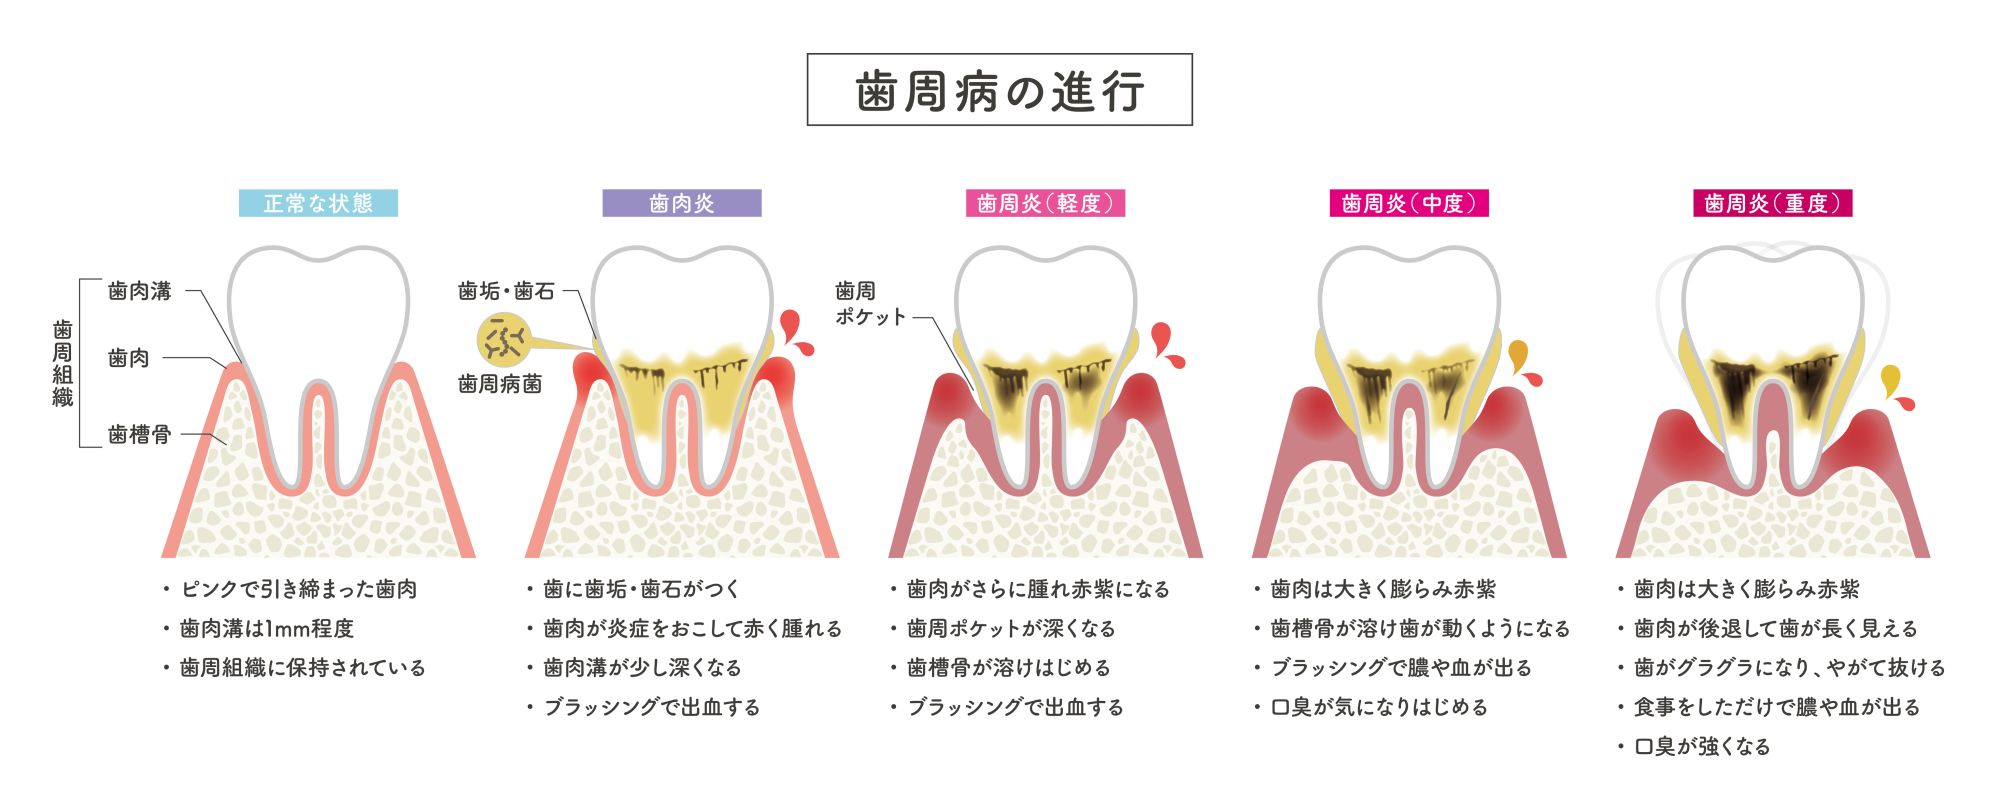

歯周病の進行

歯周病の進行と状態について

|

歯肉溝・

歯周ポケット |

状態 |

| 正常 |

1~3mm |

ピンク色に引き締まった歯茎 |

| 歯肉炎 |

3mm |

歯垢(プラーク)や歯石の細菌により、歯茎が炎症を起こし赤く腫れた状態

ブラッシングで出血する

正しいブラッシングとフロス・歯間ブラシの使用で健康な状態に戻ることが可能 |

| 歯周炎(軽度) |

3~4mm |

更に歯茎が腫れ赤黒くなり出血がある状態

歯を支える歯槽骨が溶け始める |

| 歯周炎(中度) |

4~6mm |

歯茎の腫れが赤黒く大きくなり、出血・膿が出る状態

口臭が気になるようになる

歯を支える歯槽骨が溶け歯が動くようになる |

| 歯周炎(重度) |

6mm以上 |

歯茎の腫れがより一層大きくなり歯肉が後退し歯が長く見える

出血や膿が常に出た状態

口臭が強くなる

歯槽骨が溶け歯がぐらつき最終的に抜けてしまうか抜歯となる |